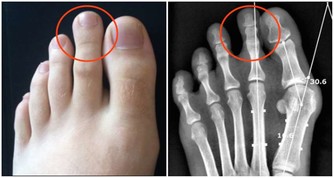

骨質疏鬆、肌肉力量差、平衡能力差。

俗話說“人老先老腿”是很有道理的,實際上從40歲開始,人的肌肉每年都在不斷地往下衰減,

那麼如果肌肉力量不足以支撐行走就會出現步態異常。

很多老年人步基很寬,如果平衡能力又不好的話就很容易跌倒。